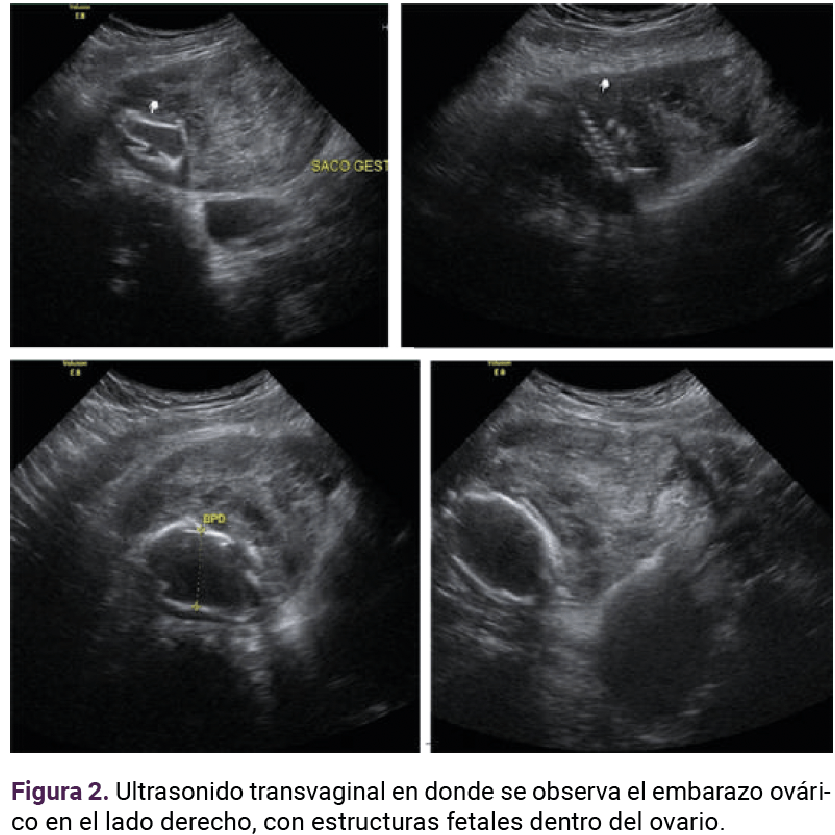

La resonancia magnética determinó el sitio de implantación: en el hueco pélvico el útero se observó en situación y morfología habitual, con diámetros máximos de 75 x 80 x 45 mm. El miometrio aparentemente homogéneo; el endometrio central, lineal e hiperintenso con espesor de 2.1 mm. El cuello uterino se apreció con adecuada intensidad de señal y sin alteraciones aparentes. En el ovario derecho se visualizó una imagen heterogénea, con estructuras fetales y la placenta con realce al paso del contraste, adherida a la pared posterior. Hubo zonas en el peritoneo parietal donde no se logró delimitar su interfaz (109 x 68 mm). El anexo izquierdo se encontró con morfología e intensidad de señal adecuadas. En la cavidad abdominal no se observaron líquido libre ni colecciones. Figuras 3 y 4

Figura 4. Resonancia magnética en plano transversal.

Si bien el ultrasonido transvaginal es un método auxiliar simple y reproducible para diagnosticar el embarazo ectópico, se menciona que el índice de diagnóstico acertado preoperatorio del embarazo ovárico con este método es solo del 18%.7 Algunos estudios reportan la utilidad de la resonancia magnética cuando los informes del ultrasonido transvaginal son insuficientes o inconclusos, sobre todo para diagnósticos específicos de embarazos ectópicos infrecuentes o complicados.11 Los hallazgos incluyen: estructuras parecidas a un saco gestacional, hematoma anexial o abdominal, dilatación tubárica debida a hemosalpix y realce de la pared tubárica.11 Cuando se carece de este recurso y no se consigue delimitar adecuadamente la localización precisa del embarazo extrauterino, lo conducente es la resonancia magnética.11